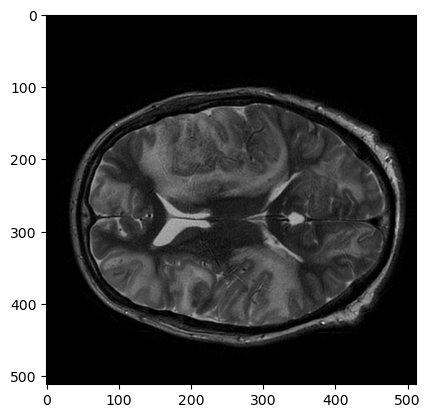

plt.imshow(t2_nib_array[:,:,t2_nib_array.shape[2]//2], cmap='gray')

t2

Это воксельный массив. Его расположение в пространстве томографа представлено в матрице аффинного преобразования: